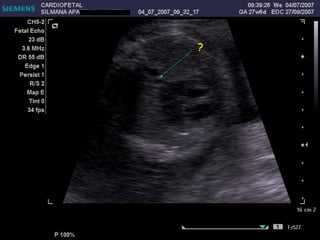

EXAMEN BASICO EXTENDIDO Corte de 3 vasos Tracto de salida izquierdo Tracto de salida derecho

OTROS CORTES

?